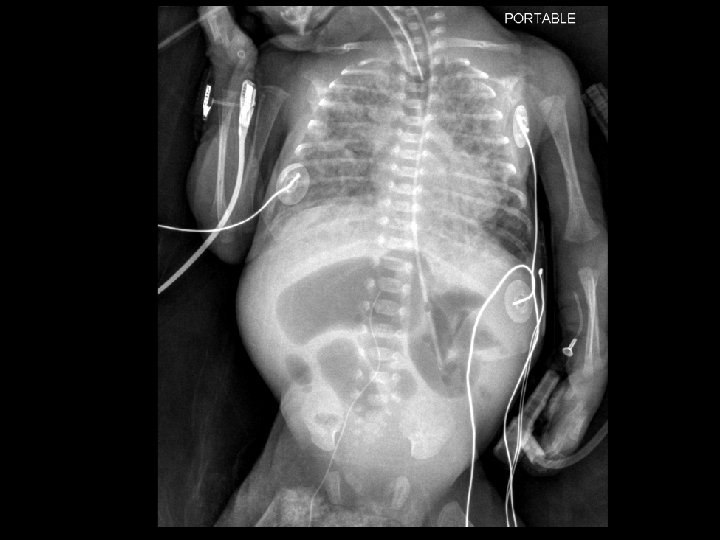

Case 1 Oh, oh…. . • On day 12…. – Free air noted on abdominal XR – No clinical abdominal symptoms • Rx…. – Intubated for transport – NPO – Antibiotic coverage expanded – Transported to Oakland Anna Bergquist CHO MR 960776

Case 1 Admission to Children’s Weight 560 g HR 157, BP 49/24 (mean 34) Grade 1/6 murmur, good pulses and perfusion Lungs unremarkable Abdomen “…full but not tense and does not appear tender. ” • Comfortable, vigorous, responsive • • • Anna Bergquist CHO MR 960776